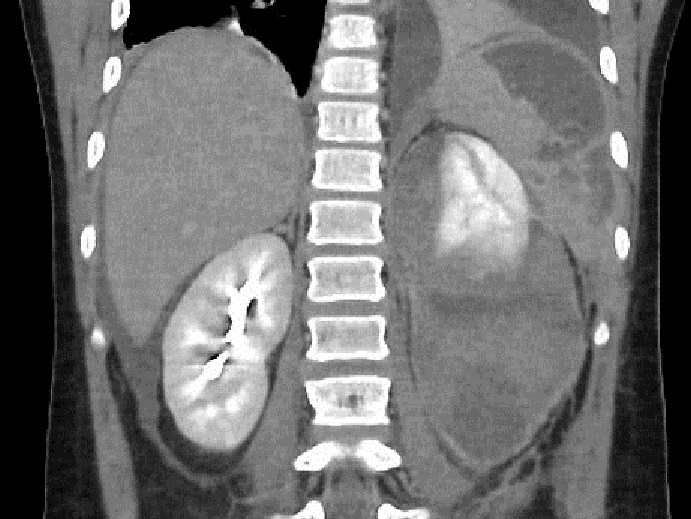

Meme cas

au temps de secretion renale |

Image radiologique traumatisme de ;la

rate grade V avec lesion de laceration corticale ,

hematome intraparenchymateuse et image de

devascularisation . Image de laceration est image de

hypodensite de dechirure la capsule ( fleche rouge )

. Image radiologique TDM Plus C+ phase veineuse . |